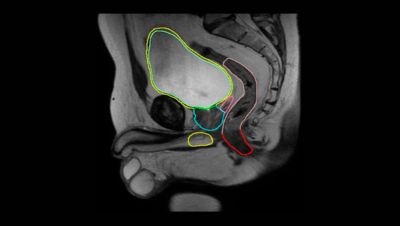

Prostate Cancer Staging